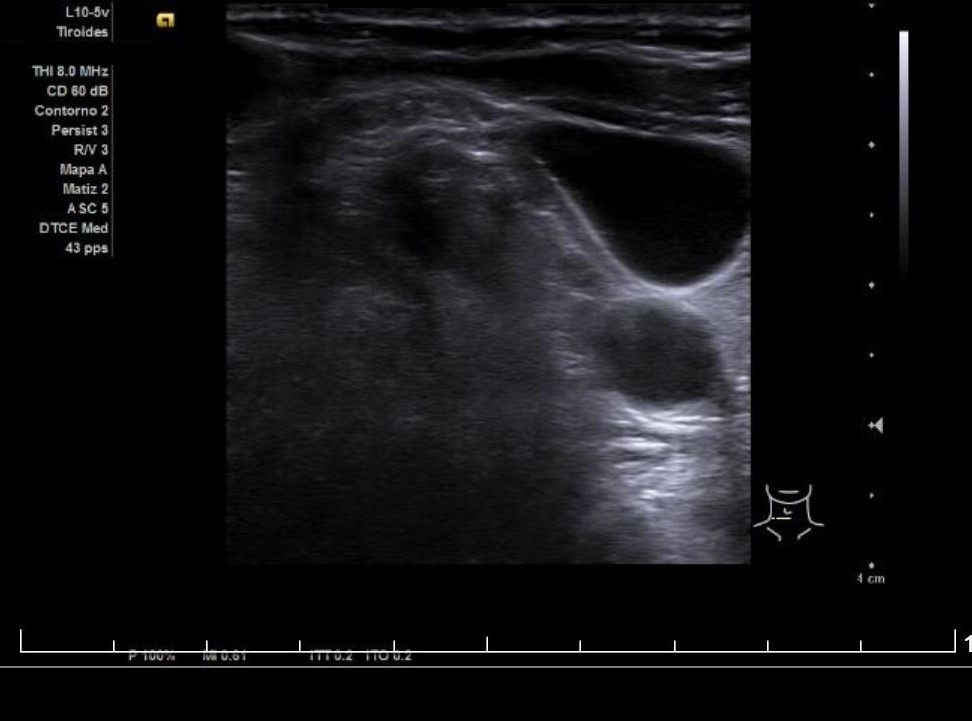

Se aprecia un tiroides de características ecográficas compatibles con tiroiditis, sin cambios respecto a ecografía previa, al igual que la grasa peritiroidea derecha, pero de manera incidental se observa un aumento del calibre fusiforme de la yugular externa derecha con respecto a la izquierda, con flujo vascular reducido.

Flebectasia yugular derecha.